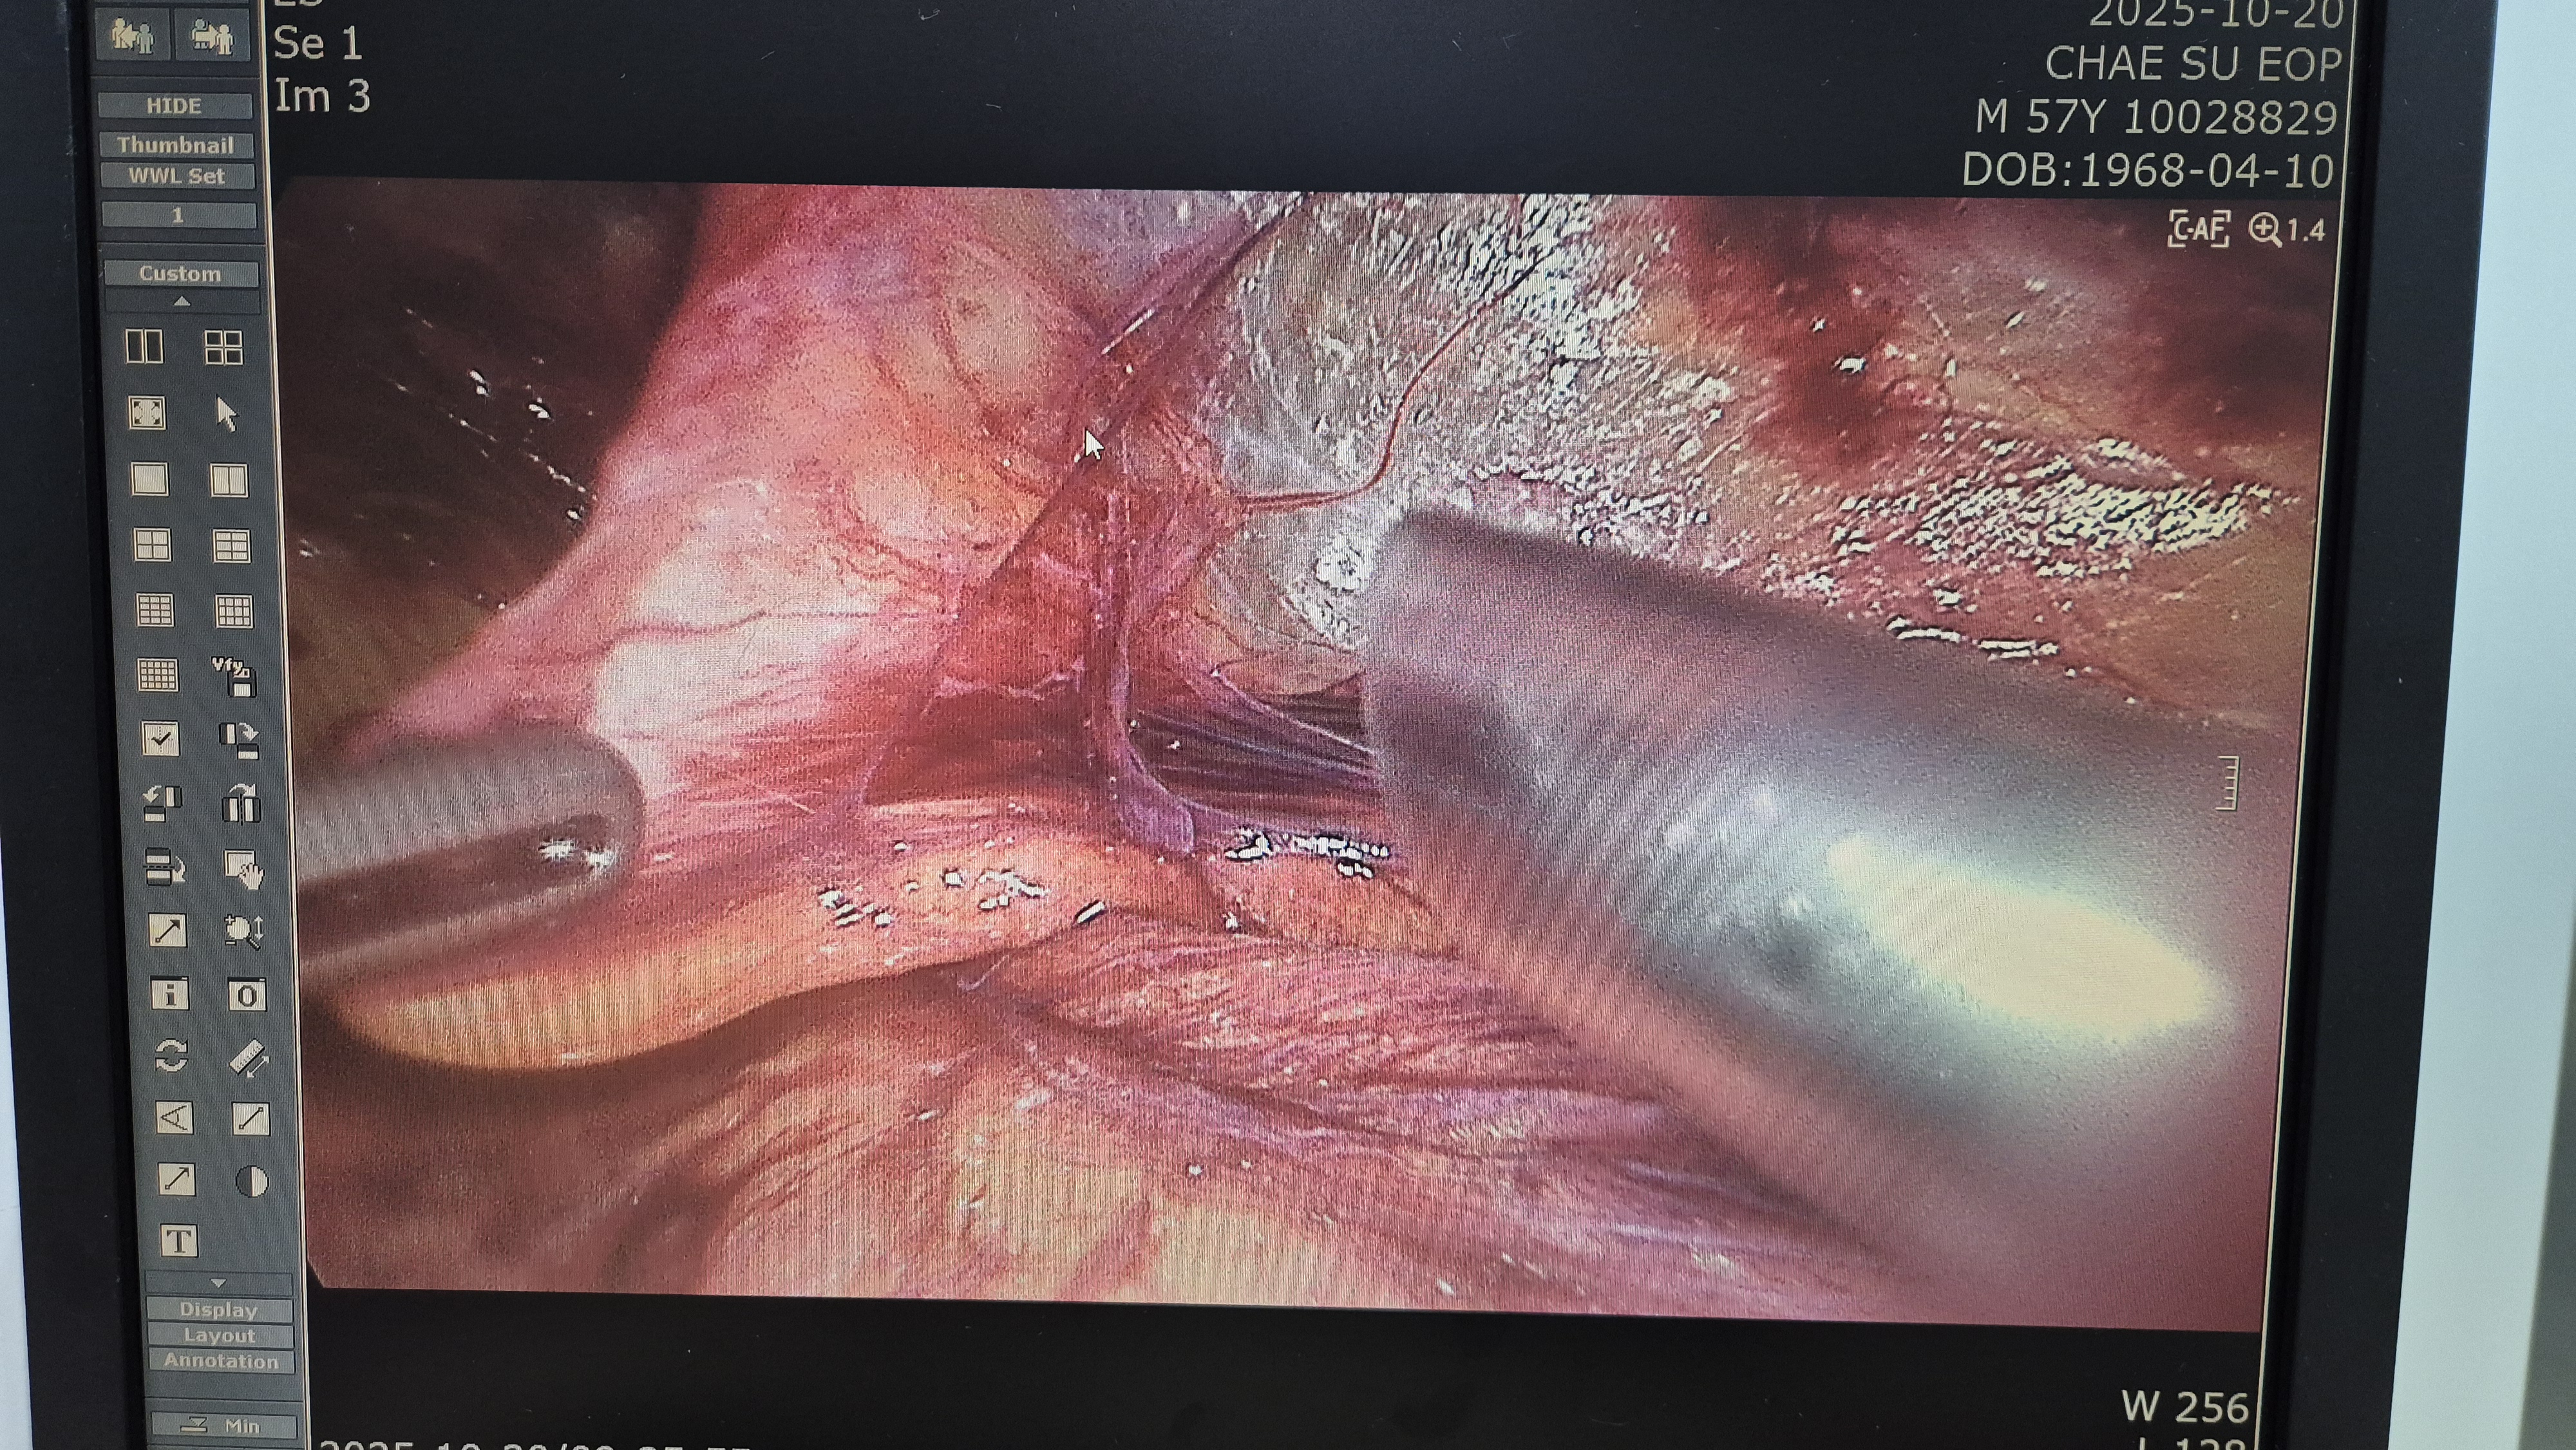

방금 복강경 탈장교정술을 시행했습니다.

탈장 확인후 박리.

메쉬로 고정.